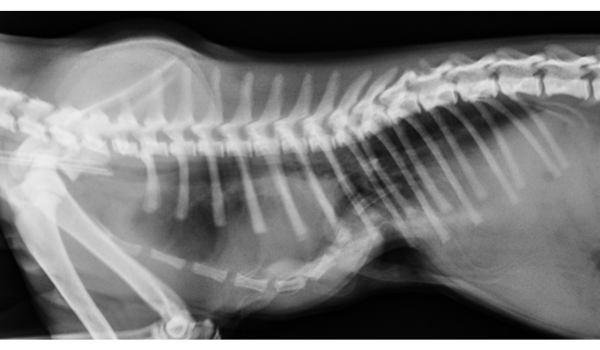

- Radiographie thoracique : permet d’évaluer la profondeur du sternum et de mesurer l’indice de gravité (indice de Haller modifié pour animaux)

- Scanner ou IRM thoracique : utile dans les formes sévères ou chez l’adulte pour planifier l’intervention chirurgicale